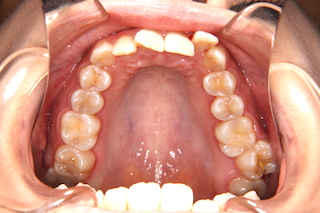

噛み合わせが深く,下の前歯が見えません!

上顎・・前歯には叢生があります